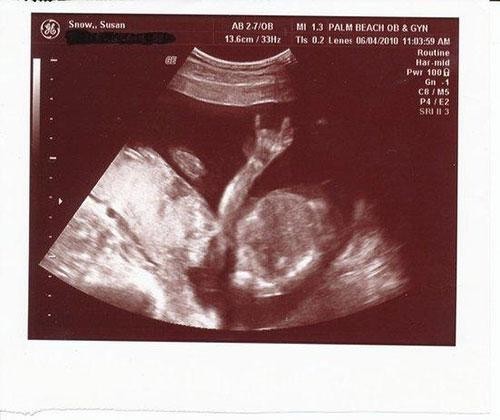

El işareti yapan bebek